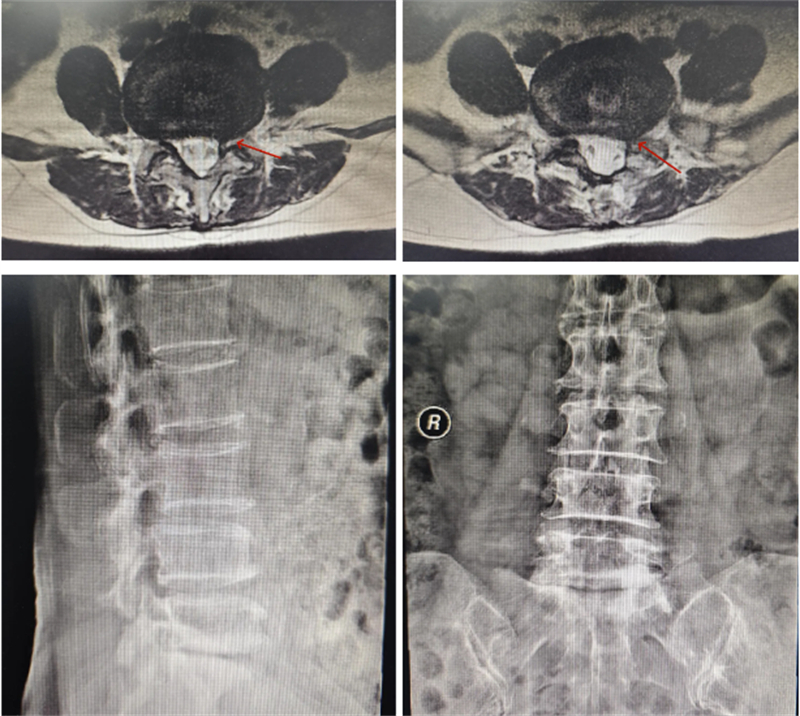

術前影像

為了徹底解決這一頑疾,許女士最終決定來到柳州市人民醫院接受治療。入院后,經過詳細的影像學檢查和臨床評估,確診其患有嚴重的腰椎管狹窄癥,神經受壓情況較為明顯。由于患者存在明顯的腰椎骨質增生,正常的解剖標志部分消失,使得手術難度大大增加。在這種情況下,如何確保置釘的精確性和對神經的有效減壓成為了手術成敗的關鍵所在。